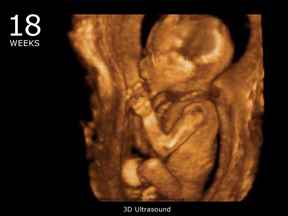

Ультразвуковое исследование: На восемнадцатой неделе часто проводится ультразвуковое исследование, которое позволяет не только оценить развитие плода, но и определить его пол. Это исследование также помогает выявить возможные аномалии и оценить состояние здоровья матери и ребенка.

Кроме изменений в теле и организме матери, происходят изменения и в организме малыша. На восемнадцатой неделе малыш уже имеет внешний вид настоящего маленького человечка. У него сформированы пальцы и фаланги рук, ножки, даже появился индивидуальный отпечаток на пальцах. Именно на этой неделе полностью видны половые органы ребенка, и родители могут узнать, кого они ожидают.

Как выглядит плод на 18 неделе беременности?

Его вес сейчас составляет 150 г, а длина – около 12-14 см. Малыш постоянно копошится, и ты, возможно, уже достаточно часто ощущаешь это. Сосудики, по которым течет кровь, отчетливо видны сквозь тонкую кожу, поэтому кожа выглядит ярко-красного цвета. Ушки заняли окончательную позицию и даже немного оттопырились.